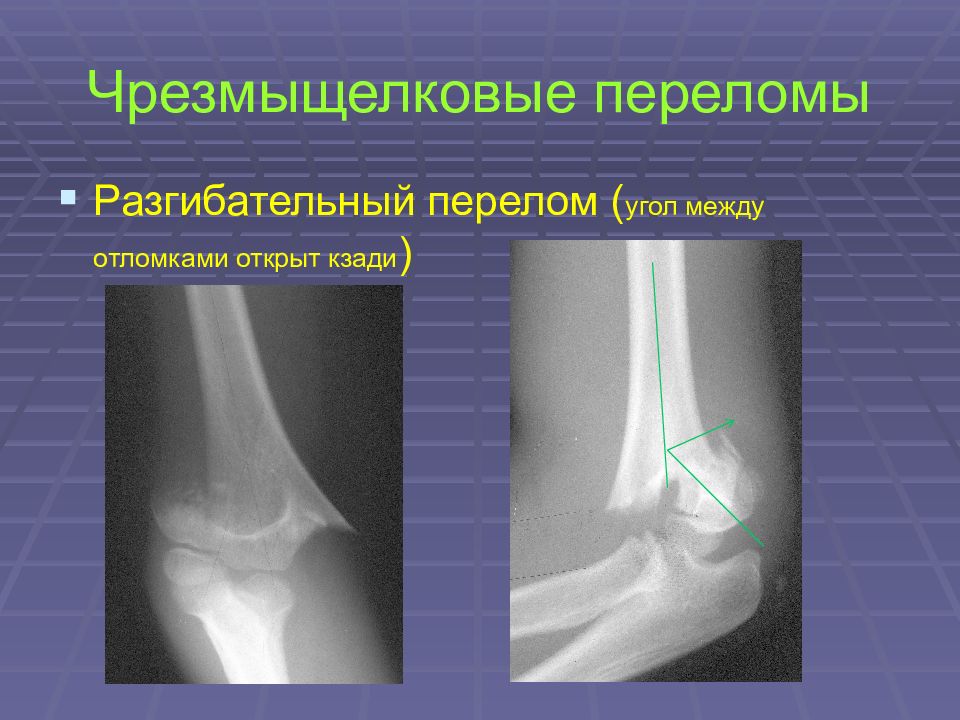

Слайд 20: Чрезмыщелковые переломы

Разгибательный перелом ( угол между отломками открыт кзади )